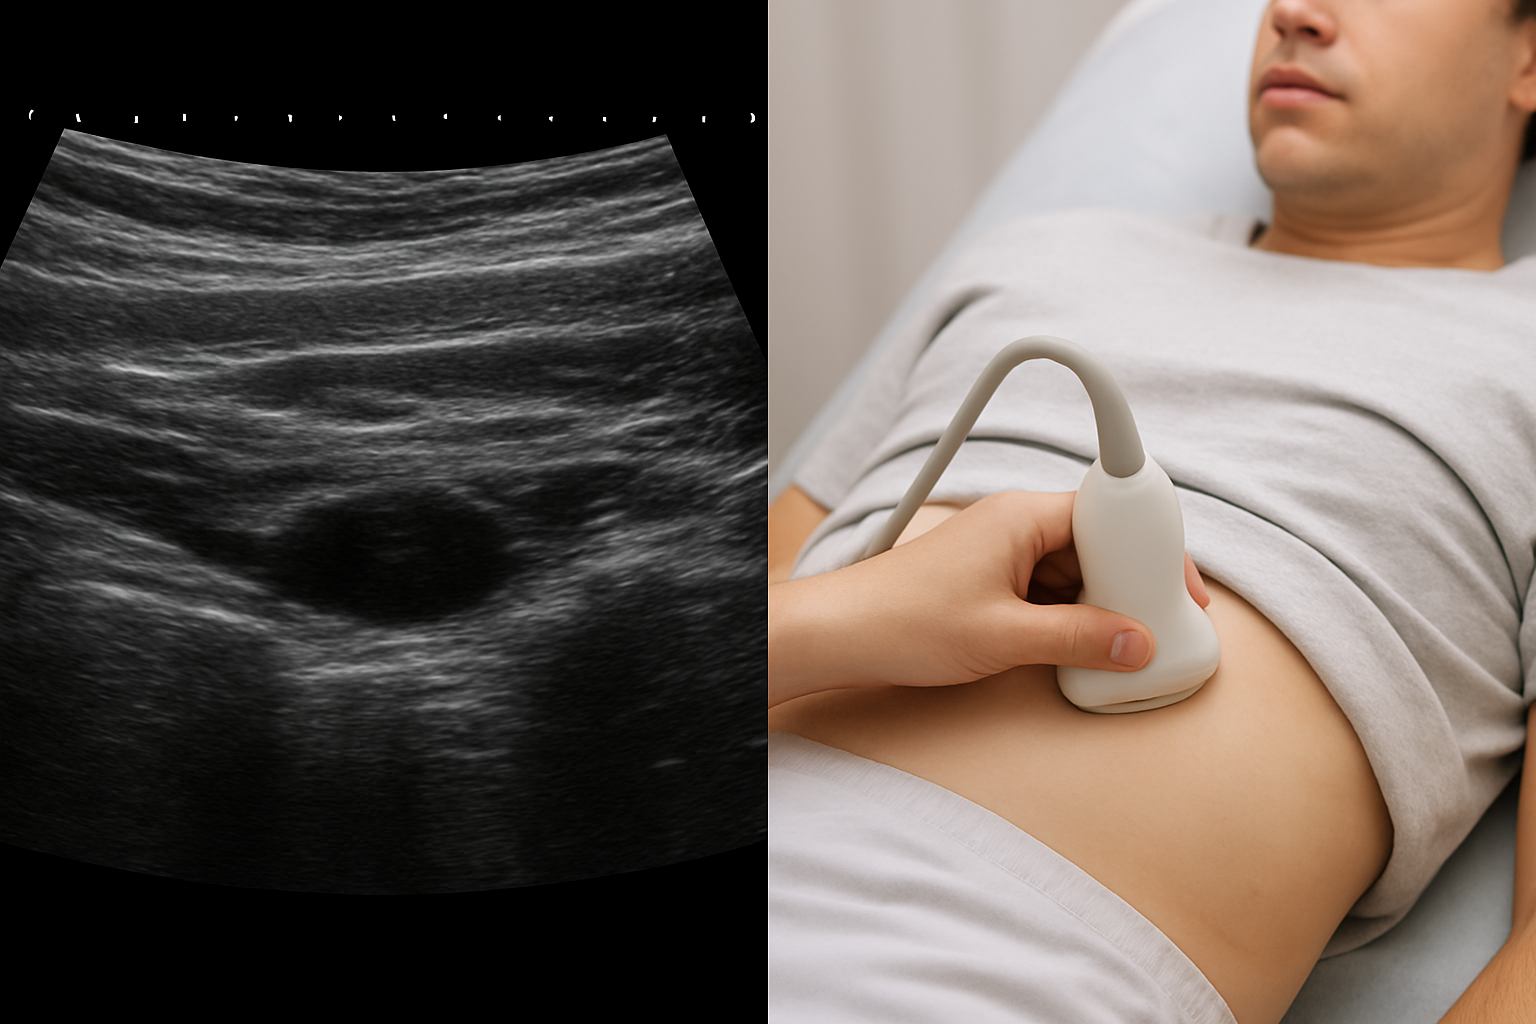

УЗИ мягких тканей – доступный и чрезвычайно информативный метод диагностики патологических образований (гигрома, липома, гемангиома и другое), локализующихся в толще мягких тканей организма (кожи с подкожной жировой клетчаткой, мышц и соединительнотканных структур, а также лимфатических узлов). Данный метод исследования

показывает размеры образования, его форму, точную локализацию, особенности строения и характер содержимого.